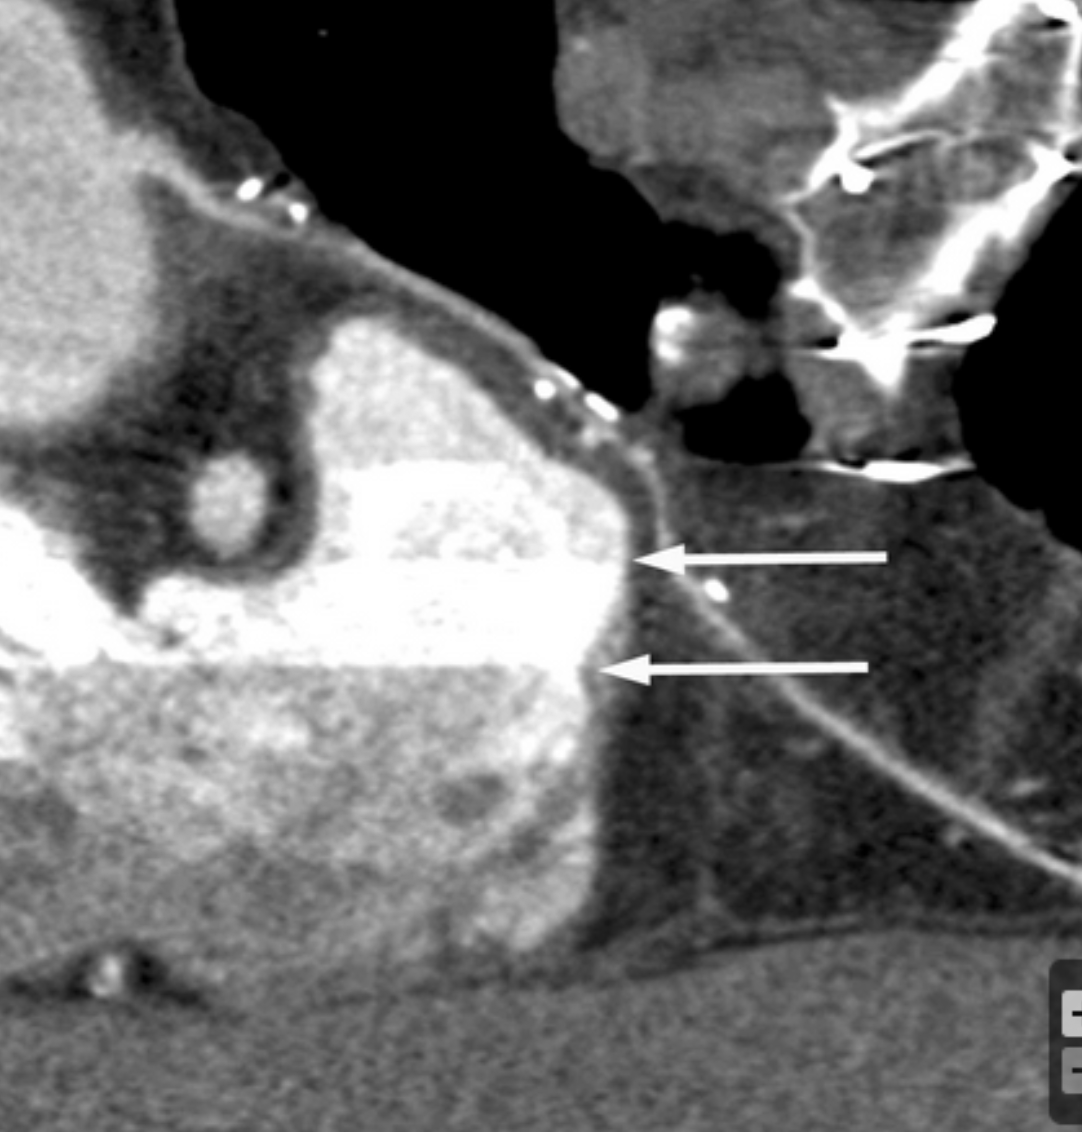

Describe the findings:

Normal inflow pattern